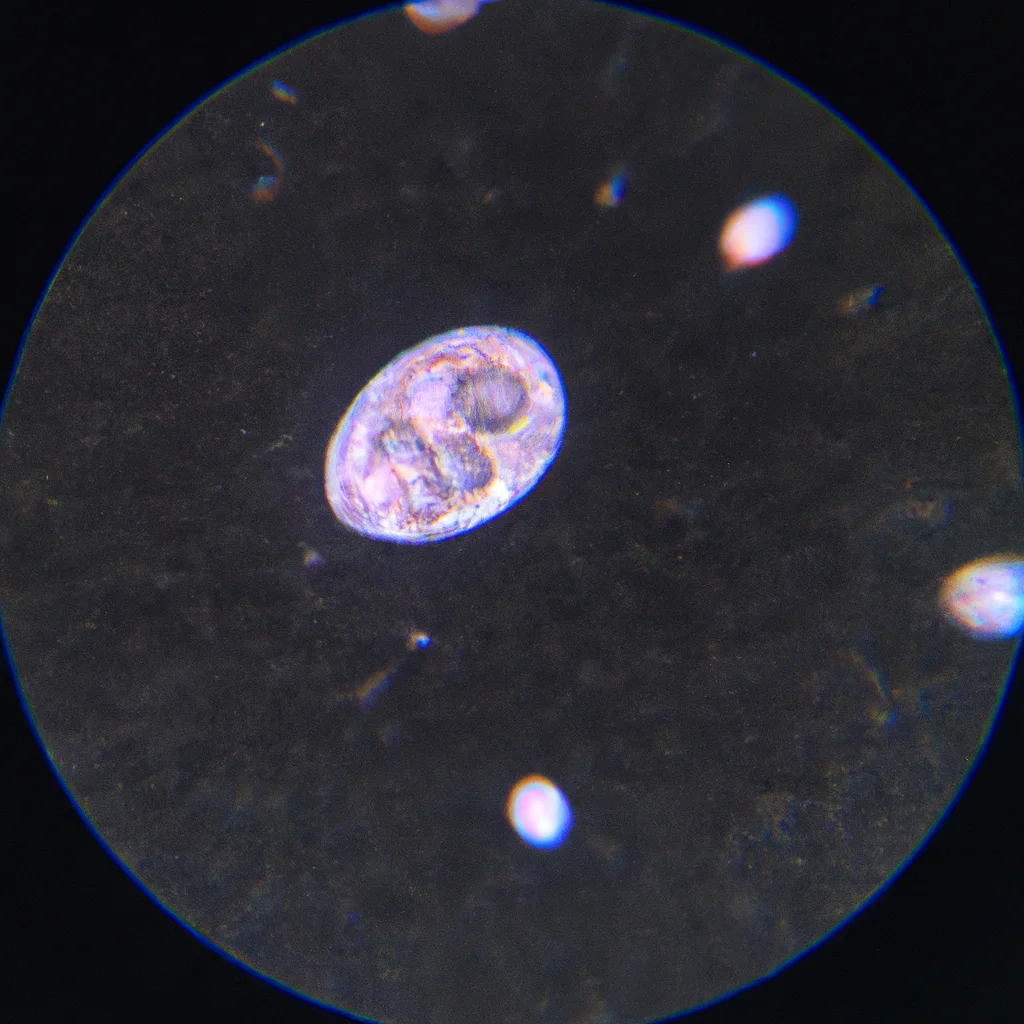

Gambar Proses Ovulasi